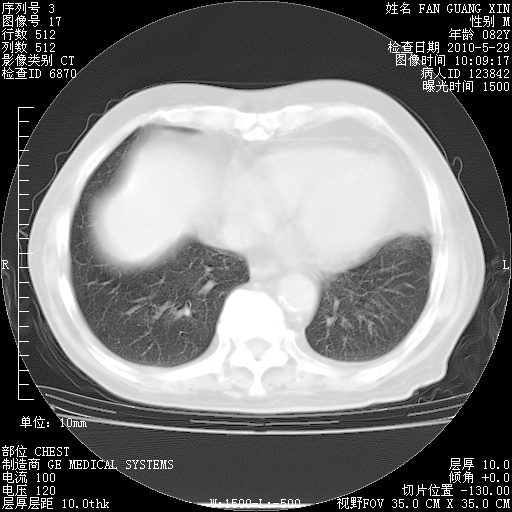

再治疗10天后的肺部CT

从白细胞总数和中性比例看好像合并感染。肺部纹理好像比上次多,支气管炎?其他感染?